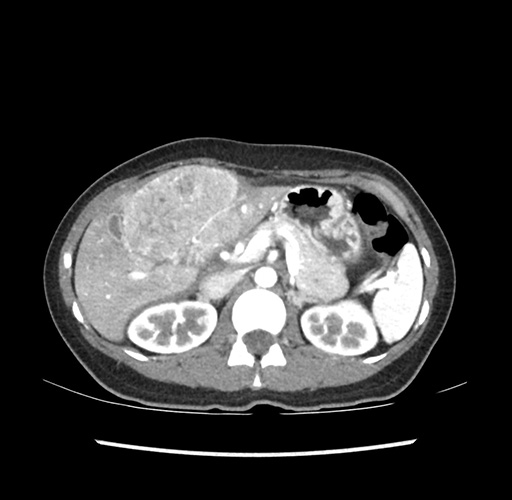

Imaging Analysis

Look through the patient's CT scan to identify any areas of concern for the necessary procedure.

Based on your CT findings, which issue(s) would give reason for "planned slowing down moment(s)" in this case?

Considering a standard left lateral sectionectomy procedure, what step(s) of the operation would you do differently in this case ?